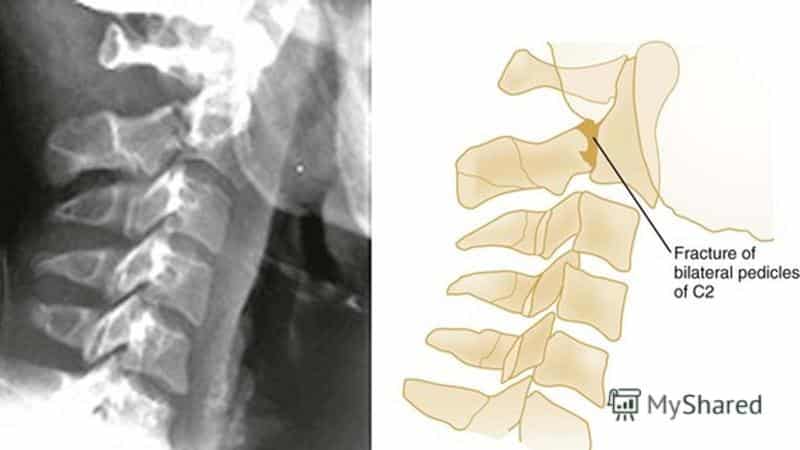

Диагностика

Диагностический процесс начинается с осмотра пациента, определения места возникновения боли и проверки неврологических рефлексов. Для оценки состояния и расположения позвонков проводится рентгенография в различных проекциях.

Для более детального анализа используются компьютерная и магнитно-резонансная томография, а также спондилография.